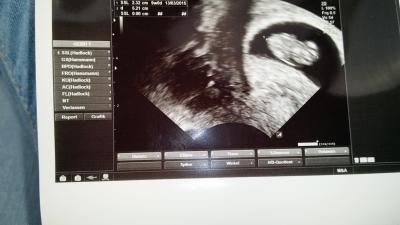

Hey liebe Mamis und bald Mamis, ich war heute beim Frauenarzt.Bin jetzt 9+0 also 10 ssw und dem kleinen würmchen gehts super.Leider macht mein FA net so schöne Fotis und mein kleiner Krümel ist auch die ganze Zeit rum gesprunge hahahaha.... das war wunderschön. Also hier mein kleines Bildchen! Jetzt hab ich den nächsten Termien erst wieder in einem Monat....ahhh.... :-P

Übringends... der Kopf ist links und er hat seine Arme und Beine nach oben gestreckt... deswegen sieht es etwas komisch aus.Er ist vom Kopf bis zum Po jetzt 2.32cm groß